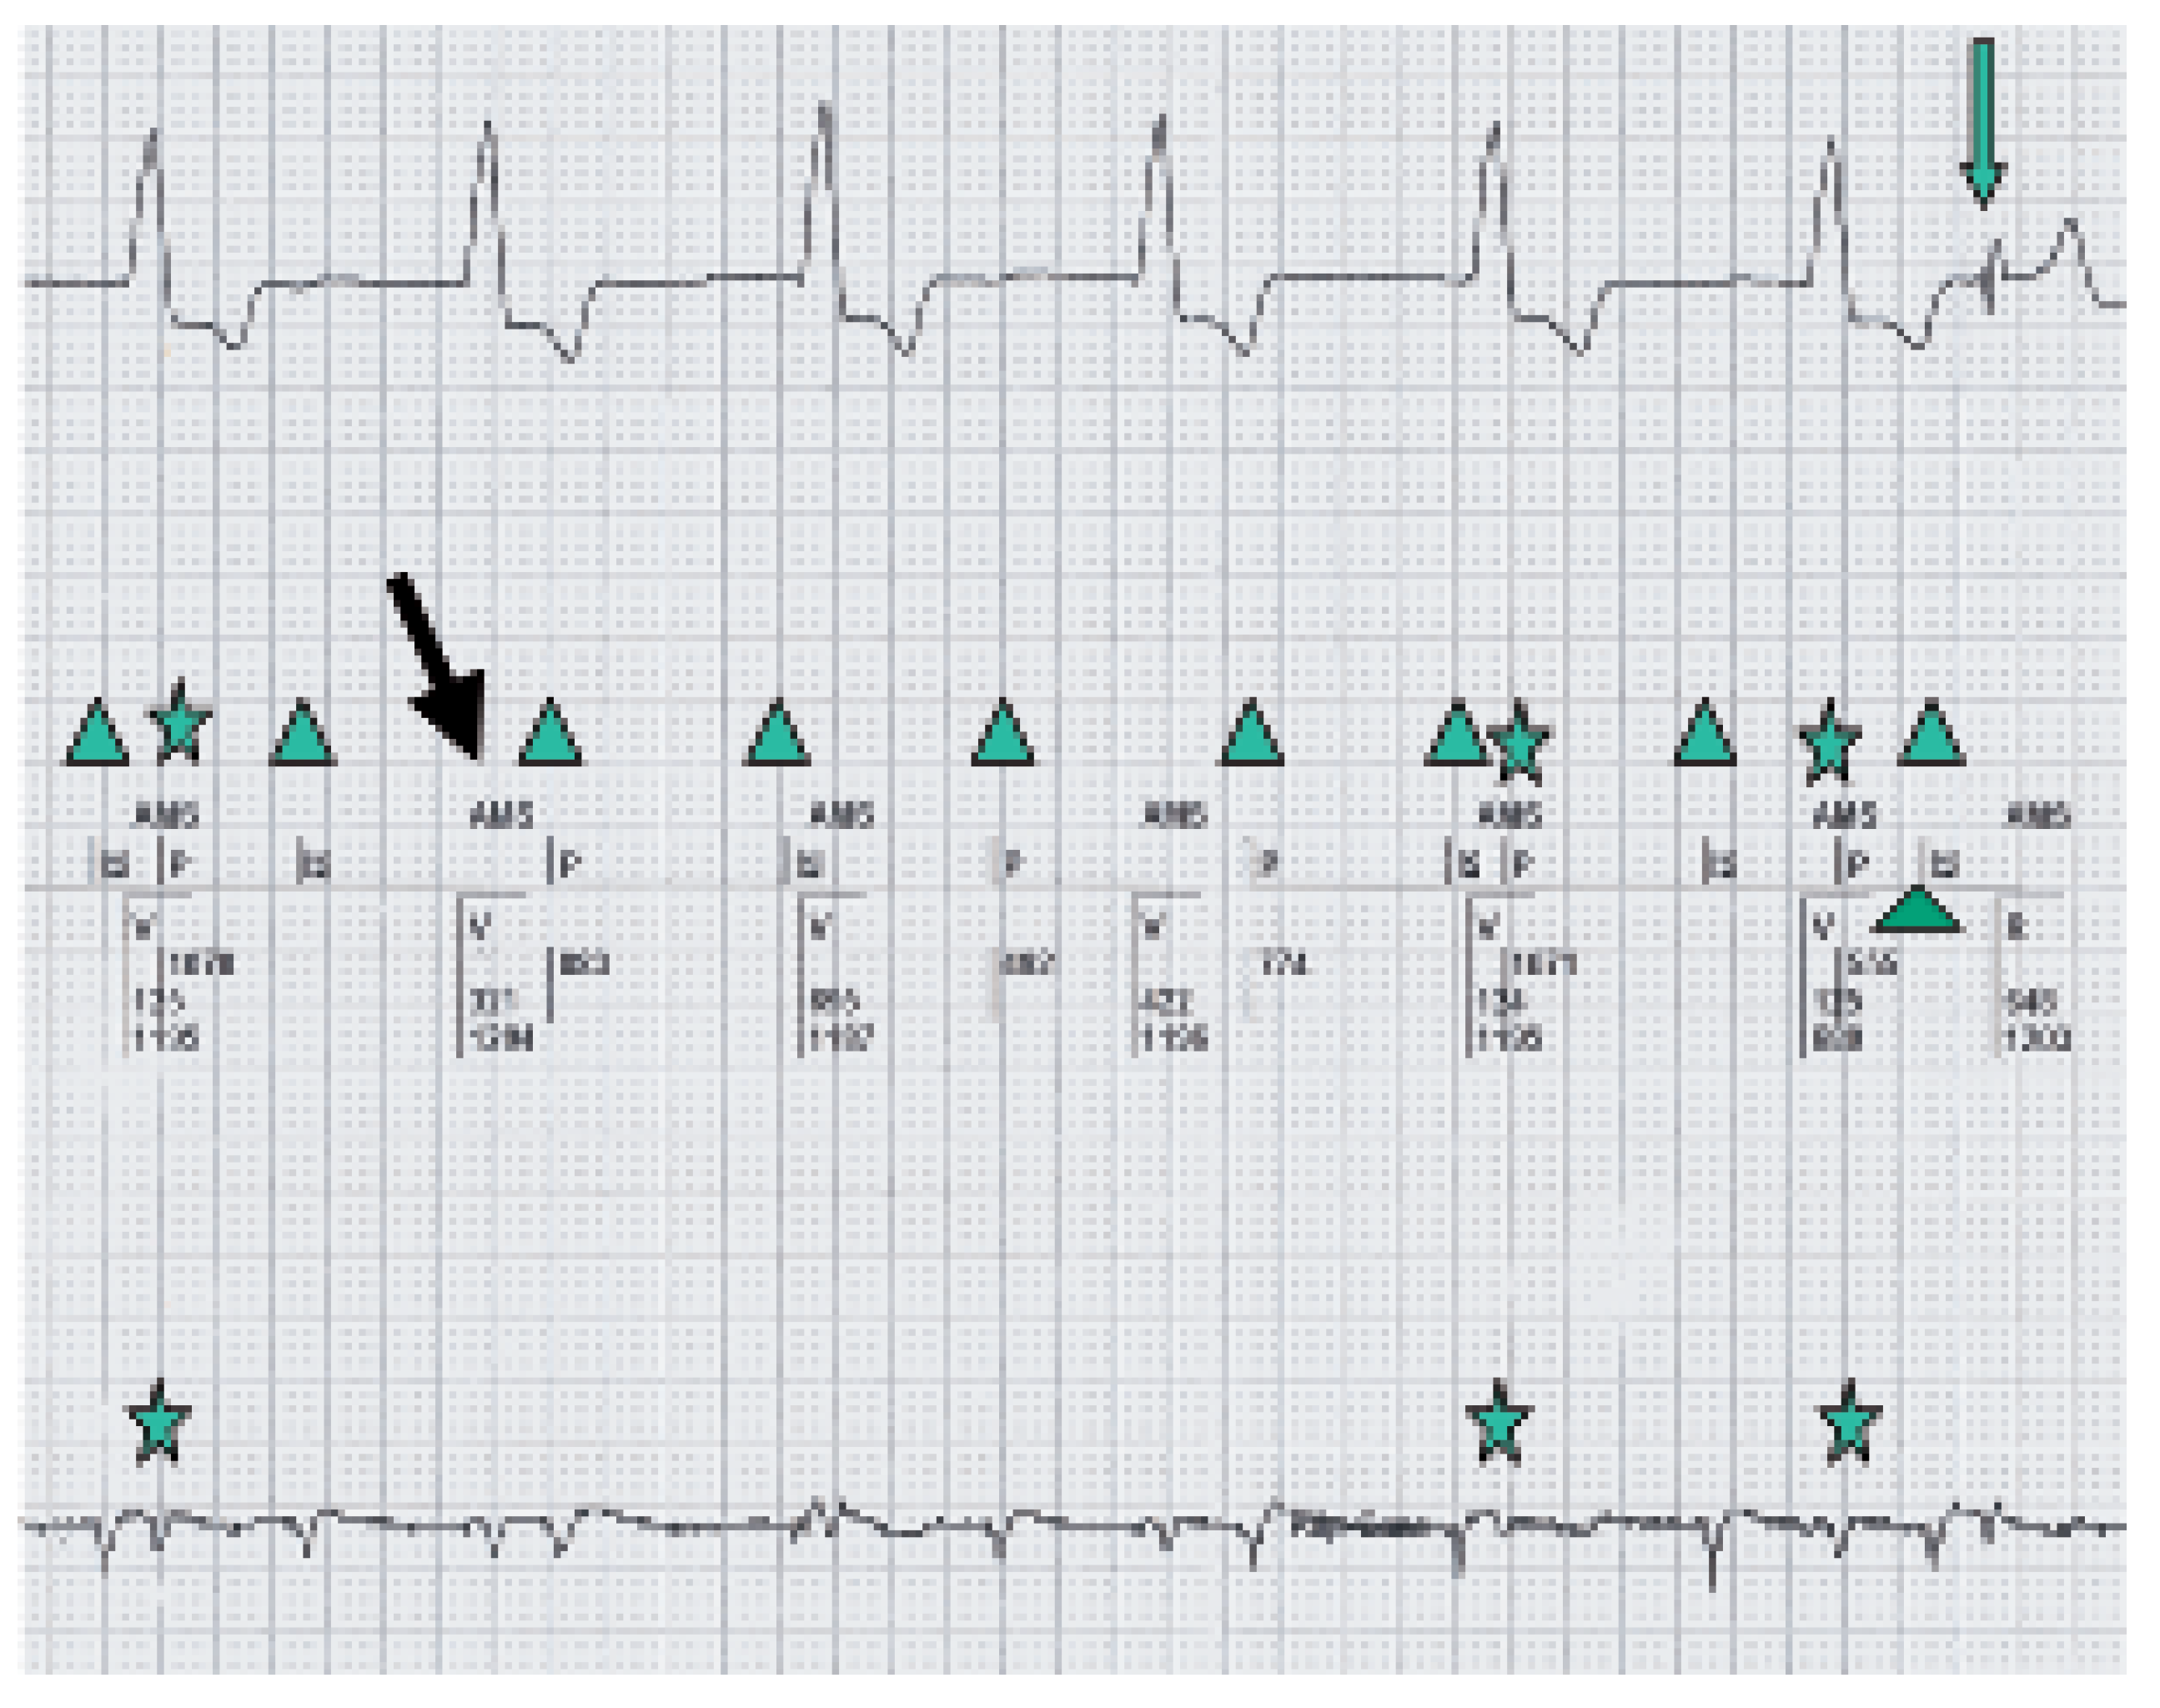

Intrinsic ventricular complexes.

P-waves.

Paced ventricular complexes in AMS with VVI back up mode of 50/min.

Switch from VVI to VDD mode with 1:1 conduction.